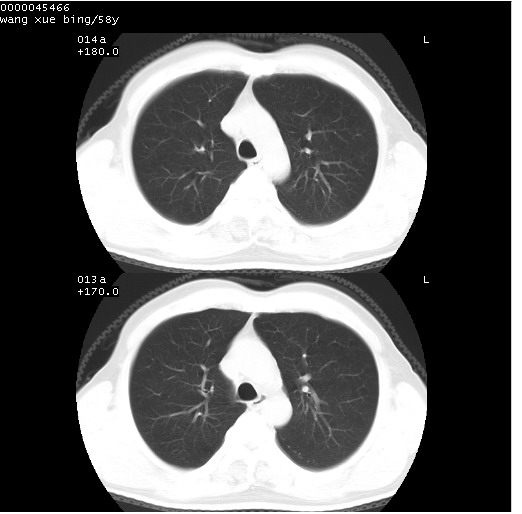

患者 男,58岁。咳嗽、咯血3月余。

胸部cr x线片提示:1)右下肺脓肿。2)右下肺周围型肺癌不排除。建议:行ct扫描检查。

胸部ct轴位平扫(层厚10mm,螺距1.5,重建间隔10mm),图像如下:

右肺下叶团块及不规则空洞,内壁不规则,外缘见粗长毛刺,临近胸膜明显增厚并与病灶关系密切。支持考虑:右肺肺脓肿!建议穿刺病理检查待除外周围型肺癌!

右肺下叶见不规则厚壁空洞,内壁不规则,外缘见粗长毛刺,临近胸膜明显增厚并与病灶关系密切。支持考虑:周围型肺癌!

右肺下叶周围型肺癌伴空洞形成!征象比较明显!分叶、毛刺、胸膜凹陷征、厚壁空洞,壁结节!

空洞壁厚,不规则,其内可见壁结节,周围可见毛刺及阻塞性炎变,多考虑癌性病变.

空洞内壁不规整,有壁结节,周围有毛刺,支持癌性空洞。